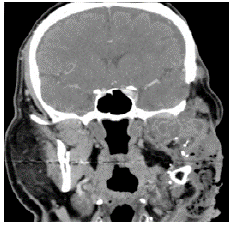

Eleven years after the initial surgery, and after 3 surgeries, a new local relapse was discovered. On physical examination, the patient was found in good condition, with left facial palsy and mass in left masticator space with extension to hard and soft palate, in addition to left submandibular ganglion conglomerate. Contrasted CT showed a mass that involved the left masticator space, lobed, of heterogeneous density with extension towards the skull and average cranial fossa of 36.7x53.6x42mm in anteroposterior section (Figures 3 and 4); biopsy and histopathological study confirmed ameloblastoma.

Follicular cystic ameloblastoma and plexi-form ameloblastoma were identified in all the pathologies analyzed since the initial biopsy and in the different surgical specimens (Figures 3 and 4), both from the local resections and the scalp lesion. No genetic profile of BRAFV600E mutation was performed, since it was not requested during the period when the samples were processed and it is not a routine test performed in the institution.